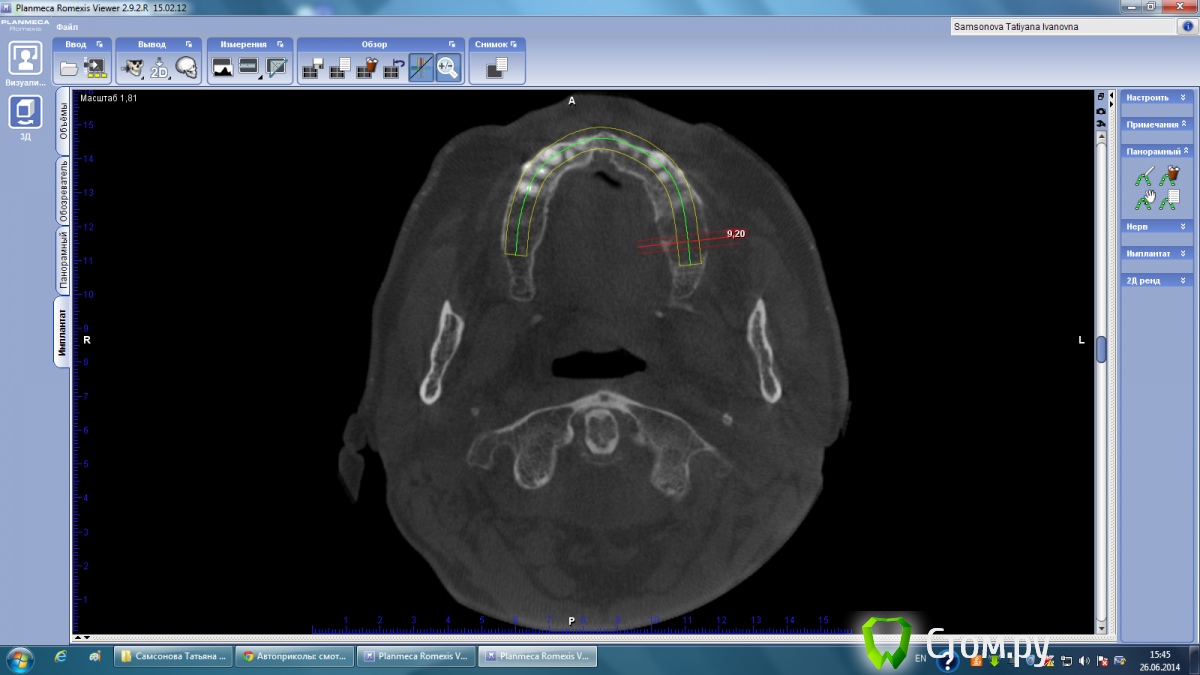

Тимур86 Опубликовано 26 июня, 2014 Поделиться Опубликовано 26 июня, 2014 пациентка пожилого возраста,хочется имплантов... Ссылка на комментарий

Mane Опубликовано 26 июня, 2014 Поделиться Опубликовано 26 июня, 2014 Вопрос автору - какие задачи вы ставите перед собой у этого пациента. Совершенно видно что нужен синус. Как вы считаете в пожилом возрасте не достаточно синуса и десны на втором этапе. И керамика розовая или чуть большеватые коронки. Оправдан здесь огород с костной пластикой. Если вертикалить то ламинаты или сетка или тайтэниум реинфорсд мембрэйн. Самое простое решение конечно же с сеткой. Но самые высокие риски прорезывания (у меня). Ждем ваши ответы. 1 Ссылка на комментарий

Тимур86 Опубликовано 26 июня, 2014 Автор Поделиться Опубликовано 26 июня, 2014 Ждем ваши ответы.согласен совершенно,естественно хочется минимизировать объемы костной пластики(и не только у пожилых пвциентов)но не снизит ли срок службы имплантов такое соотношение имплант/коронка в "псевдокости"? Ссылка на комментарий